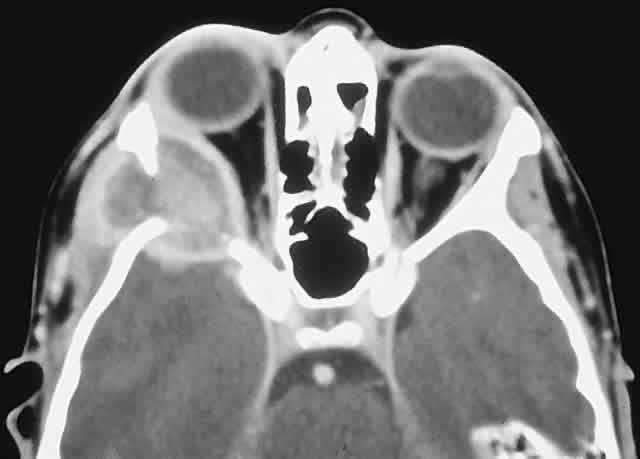

IMAGING. A mixed lytic and sclerotic mass with indistinct margins is the usual CT appearance (Fig. 9). Soft tissue infiltration of the orbit may also be evident, and the mass may contain foci of mineralization, producing fluffy densities. MRI can be of value in delineating the extent of any soft tissue component.12,116,117

Fig. 9. A painful right inferior orbital mass effect developed over several weeks in this 19-year-old man with a history of bilateral retinoblastoma treated with radiation therapy and chemotherapy. A and B. CT showed an irregular, largely sclerotic mass involving the orbital floor. He was treated with an en bloc orbitectomy and chemotherapy but died 4 years later from acute myeloid leukemia. C. Histology revealed a sarcomatous stroma with osteoid production forming lacelike patterns (hematoxylin-eosin, × 20). D. A high-power view of the sarcoma adjacent to extraocular muscle indicates that the anaplastic cells appear less atypical with incorporation into the osteoid, the so-called normalization of malignant osteoid (hematoxylin-eosin, × 50).

HISTOPATHOLOGY. Gross specimens contain infiltrative tumor, which may be white, tan, or hemorrhagic in parts, with a soft to firm or gritty texture, depending on the stromal components. The stroma contains sarcomatous cells and must show at least some foci of osteoid production. The anaplastic cells may subsume a variety of histologic subtypes, including osteoblastic, chondroblastic, and fibroblastic. In most high-grade lesions, the cells are markedly malignant, but they become less so when incorporated into the osteoid (so-called normalization of malignant osteoid). The osteoid itself may assume a characteristic delicate filigreed or lacelike pattern.40